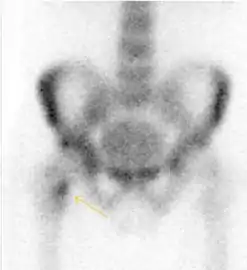

Figure 10:

Stress femoral neck fracture in a young athlete barely visible in X-ray film as a sclerotic line (arrow)[1]

In this case, Tc 99 scintigraphy shows a band of uptake[1]

Furthermore, T1 (left) and DP fat saturated (right) weighted MR images showed the fracture line and a pattern of edema.[1]

Bone scanning in people with hip pain can be complementary to other imaging studies, mainly in indeterminate bone lesions to clarify whether it is an active lesion with abnormal radiotracer accumulation. Nevertheless, MRI has replaced scintigraphy in the diagnosis of most of these conditions. An example is stress or insufficiency fractures: increased uptake is usually present in around 80% of fractures within 24 h, and 95% of fractures reveal activity by 72 h following trauma, showing an overall sensitivity of 93% and specificity of 95%. MRI is superior to bone scans in terms of sensitivity (99%-100%) and specificity (100%). Moreover, a bone scan does not provide detailed anatomical location of the fracture, and further imaging is usually required.[1]